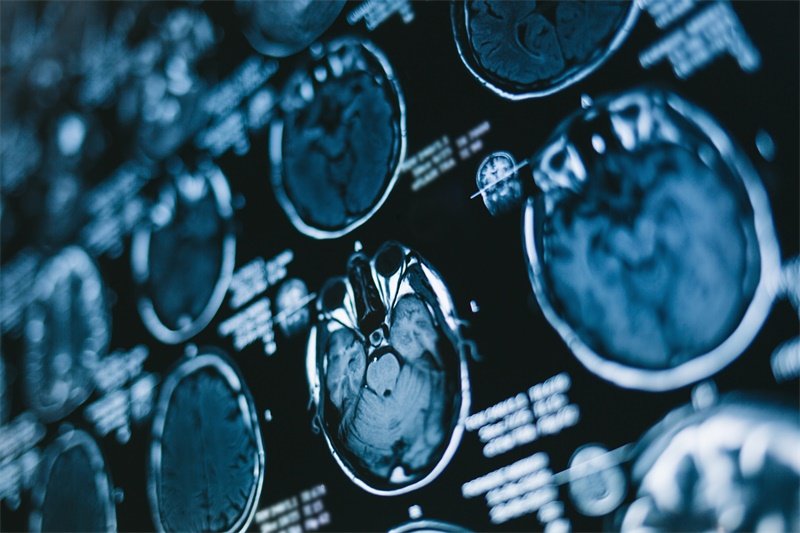

判断占位的性质通常需要结合影像学检查(如CT或MRI)、病史采集以及必要的组织活检。影像学检查可以提供病变的大小、形态及位置等信息,而组织活检可以直接判断病变的细胞组成及其性质。